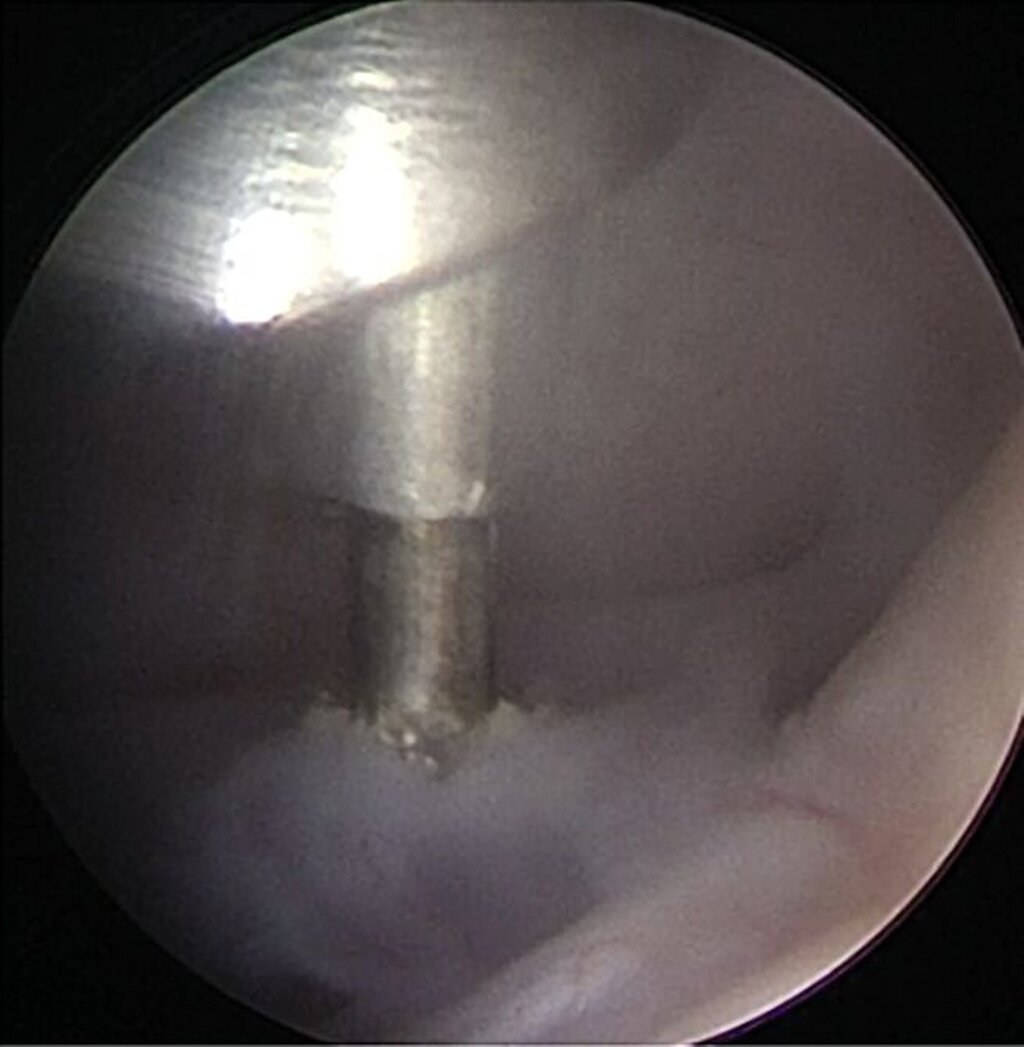

Für die Kiefergelenksarthroskopie ist eine strukturierte Orientierung innerhalb des oberen Gelenkkompartiments essenziell. Hierfür haben sich die sogenannten „seven points of interest“ nach McCain etabliert (Abbildung 3) [Srouji et al., 2018]. Diese sieben anatomischen Referenzpunkte dienen der systematischen Beurteilung des Gelenks während des arthroskopischen Eingriffs. Zunächst werden das mediale synoviale Band und der Pterygoid-Schatten („pterygoid-shadow“) als Orientierungspunkte identifiziert. Es folgen die bilaminäre Zone – eine häufige Schmerzquelle – sowie die hintere Schräge der Gelenkeminenz. Die Beurteilung des Discus articularis gibt Auskunft über Verlagerungen und degenerative Prozesse. Es folgt die Beurteilung der intermediären Zone, die besonders anfällig für eine Perforation ist. Abschließend erfolgt die Begutachtung des vorderen Recessus. Dieser stellt den Eintritt der Punktionsstelle des Level-II-Zugangs dar [Srouji et al., 2018].